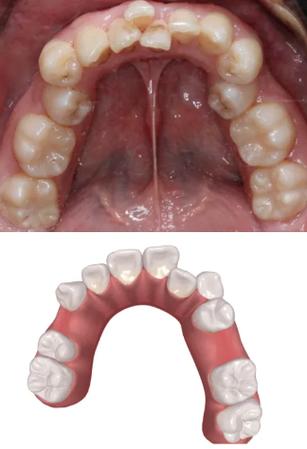

牙齿拥挤是最常见的错颌畸形之一,主要源于颌骨发育空间不足与牙齿数量、大小的矛盾,正常情况下,每颗牙齿需要一定的“生态空间”,当颌骨长度无法容纳所有牙齿时,就会出现牙齿重叠、扭转、错位,上颌牙弓长度不足时,侧切牙可能萌出不全(埋伏或过小),前牙向唇侧突出形成“龅牙”,后牙可能因拥挤而扭转,影响清洁甚至导致龋齿,拔除1-4颗前磨牙(通常为第一或第二前磨牙),可为剩余牙齿提供排齐所需的空间,通过正畸技术(如滑动机制或关闭曲),牙齿会向拔牙间隙缓慢移动,最终达到整齐排列的状态,这一过程需严格遵循牙槽骨改建规律,确保移动过程中牙齿周围组织稳定,避免损伤。